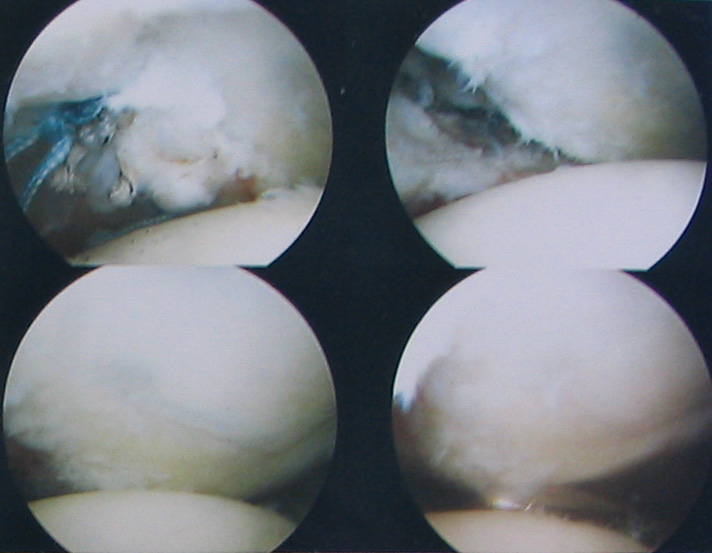

Internal shoulder photos Look away now if you don’t like seeing icky stuff. The following photos are of the internals of my shoulder as seen through an athroscopic probe during a Bankhardt repair performed in late November.